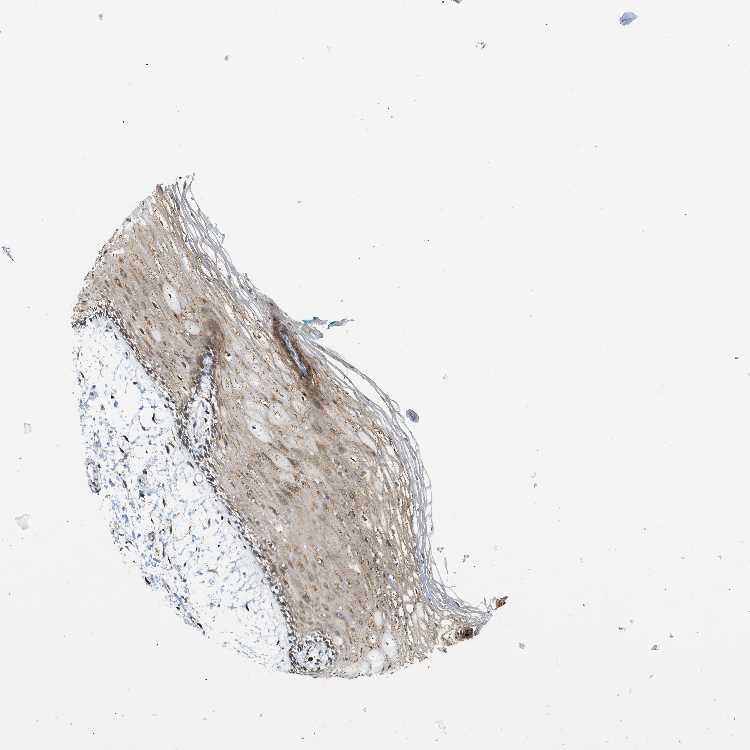

TISSUE PRIMARY DATA ORAL MUCOSA Show tissue menu

ORAL MUCOSA - Antibody stainingi

Antibody staining in the annotated cell types in the current human tissue is reported as not detected, low, medium, or high, based on conventional immunohistochemistry profiling in selected tissues. This score is based on the combination of the staining intensity and fraction of stained cells.

Each image is clickable and will lead to virtual microscopy that enables deeper exploration of all samples and also displays staining intensity scores, fraction scores and subcellular localization as well as patient and tissue information for each sample.

Antibody HPA015662Antibody HPA023277

Squamous epithelial cells MediumMedium